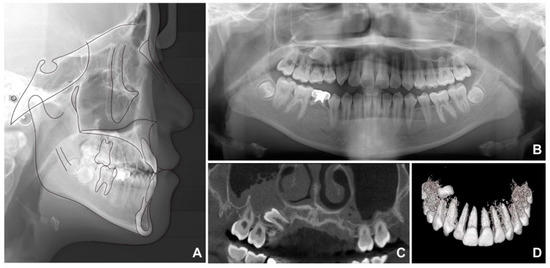

Lateral cephalometric analysis showed an SNA (angle formed by the lines connecting the sella, nasion, and point A) of 70.9°, an SNB angle of 72.7°, and an ANB angle of −1.9° (Table 1 and Figure 2A). Both the maxillary and mandibular incisors were lingually inclined, while the upper lip was retruded according to Ricketts’ esthetic line. The cervical vertebrae maturation index (CVMI) indicated that the patient was between stages 5 and 6 and had surpassed the maximum growth period. Panoramic radiography showed that the maxillary right second premolar was inversely impacted (Figure 2B) and the mandibular right second premolar was congenitally missing, with retained maxillary and mandibular primary second molars. Cone beam computed tomography (CBCT) was performed to determine the exact location of the maxillary right second premolar (Figure 2C,D). As shown in Figure 2C, it was clearly confirmed that the radiopacity of the maxillary sinus around the right impacted tooth was increased differently from that of the left maxillary sinus. Therefore, the reverse direction of the premolar towards the maxillary sinus caused perforation of the sinus wall, resulting in right sinusitis.

Figure 2. Pretreatment radiographs: (A) lateral cephalogram; (B) panoramic radiograph; (C,D) cone beam computed tomography.